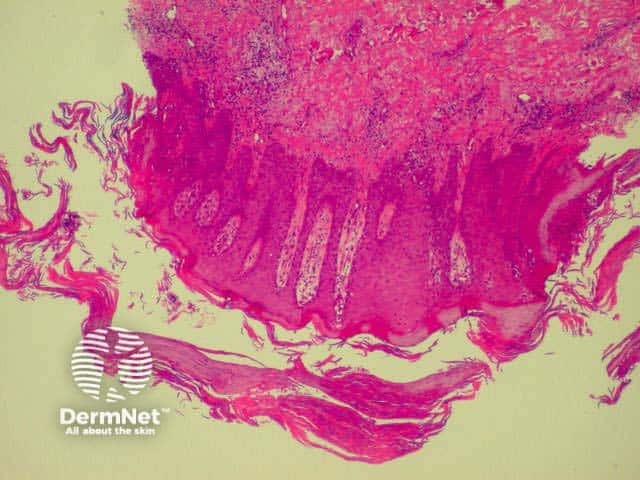

Lichen planus is the idiopathic version of a group of lichenoid disorders characterised by scaling papules or plaques. Link to a clinical description of lichen planus.

The histological features of lichen planus are:

Lichen planus Lichen planus Lichen planus Lichen planus Lichen planus Lichenoid inflammation